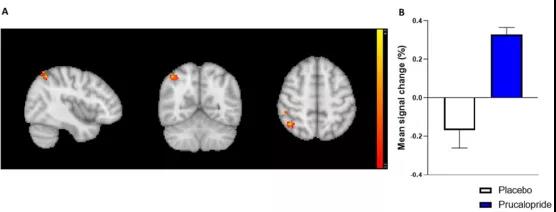

?牛津科學(xué)家發(fā)現(xiàn):通便也能通記憶,這種藥物或可促認(rèn)知作用

眾所周知,很多精神疾病常常伴隨著認(rèn)知功能障礙,認(rèn)知障礙不僅局限于記憶缺陷,還包括學(xué)習(xí)、注意力、語言以及處理速度等方面的障礙。這類障礙會對生活質(zhì)量產(chǎn)生相當(dāng)大的負(fù)面影響,所以迫切需要開發(fā)可以改善與精神疾病相關(guān)的認(rèn)知缺陷的治療方法。